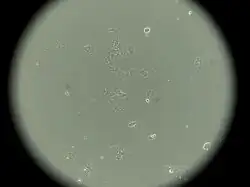

MCF-7

MCF-7 is a breast cancer cell line isolated in 1970 from a 69-year-old woman.[1] MCF-7 is the acronym of Michigan Cancer Foundation-7, referring to the institute in Detroit where the cell line was established in 1973 by Herbert Soule and co-workers.[2] The Michigan Cancer Foundation is now known as the Barbara Ann Karmanos Cancer Institute.[3]

MCF-7 cells have the following characteristics:[2][6][7][9][10][11]

- Primary tumor (invasive breast ductal carcinoma)

- Originate from pleural effusion

- Estrogen receptors present[12]

- Proliferative response to estrogens

- Presence of progesterone receptors

- Contains 17β-estradiol-binding protein[8]

- Cannot have ERBB2 gene amplification (with Her2/neu protein overexpression)

- Tumorigenic in mice but only with estrogen supplementation if engrafted into the subcutaneous fat or mammary fat pad

- Tumorigenic in mice without estrogen supplementation if engrafted intraductally[13]

- Luminal epithelial phenotype

This cell line retained several characteristics of differentiated mammary epithelium, including the ability to process estradiol via cytoplasmic estrogen receptors and the capability of forming domes.